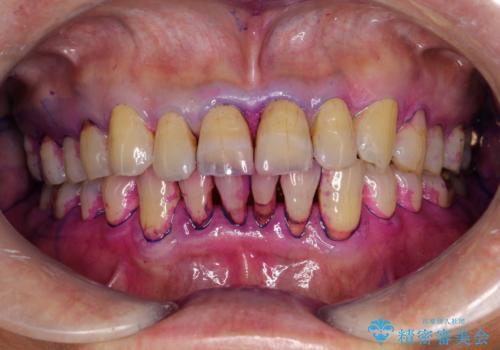

- 2カ月ごとにメンテナンスにいらしている方です。染め出しをしての歯磨きチェックとPMTC30分コースを行いました。

しかし、プラークは歯の色と似ているため、見ただけでは付着しているかどうかがハッキリとは分かりません。

染め出し液を使ってプラークを染め出すことにより、普段の歯みがきで磨き残している場所を目で確かめることができます。

日々の歯磨きを上達するには、まずどこが磨けていないか認識することが大切です。